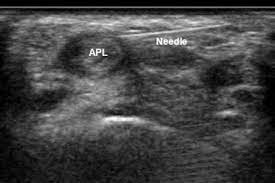

- Platelet Rich Plasma : PRP works by harnessing the healing properties of platelets. Ultrasound guided Prp is injected into the affected tendon sheath under ultrasound guidance. PRP can accelerate the natural healing process, reduce inflammation, and promote tissue repair.

Ultrasound guided Prp injection for De Quervain’s Tenosynovitis